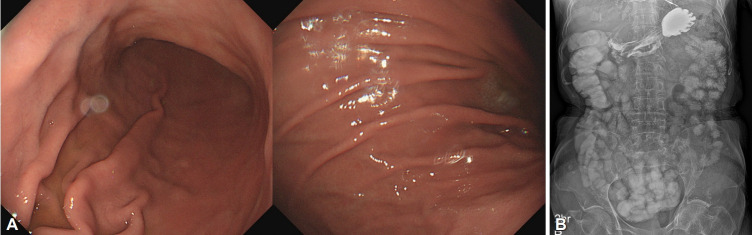

Bezoars, including phytobezoars, trichobezoars, and pharmacobezoars, are accumulations of undigested substances in the gastrointestinal tract. We report three cases of gastric bezoars. Case 1: An 86-year-old woman presented with a one-month history of abdominal pain and vomiting. Esophagogastroduodenoscopy revealed gastric bezoars; consumption of 2 L of cola daily for 2 weeks resulted in complete disappearance of the bezoars. Case 2: An asymptomatic 63-year-old woman underwent esophagogastroduodenoscopy, which revealed a gastric bezoar. Cola spraying and endoscopic lithotomy were ineffective; therefore, the patient underwent laparoscopic removal of the bezoar for management of small bowel obstruction secondary to the bezoar fragments. Case 3: A 6-year-old girl with a history of pica underwent two laparoscopic surgeries 10 months apart for recurrent trichobezoars. We report our treatment approach in three patients who presented with gastric bezoars.